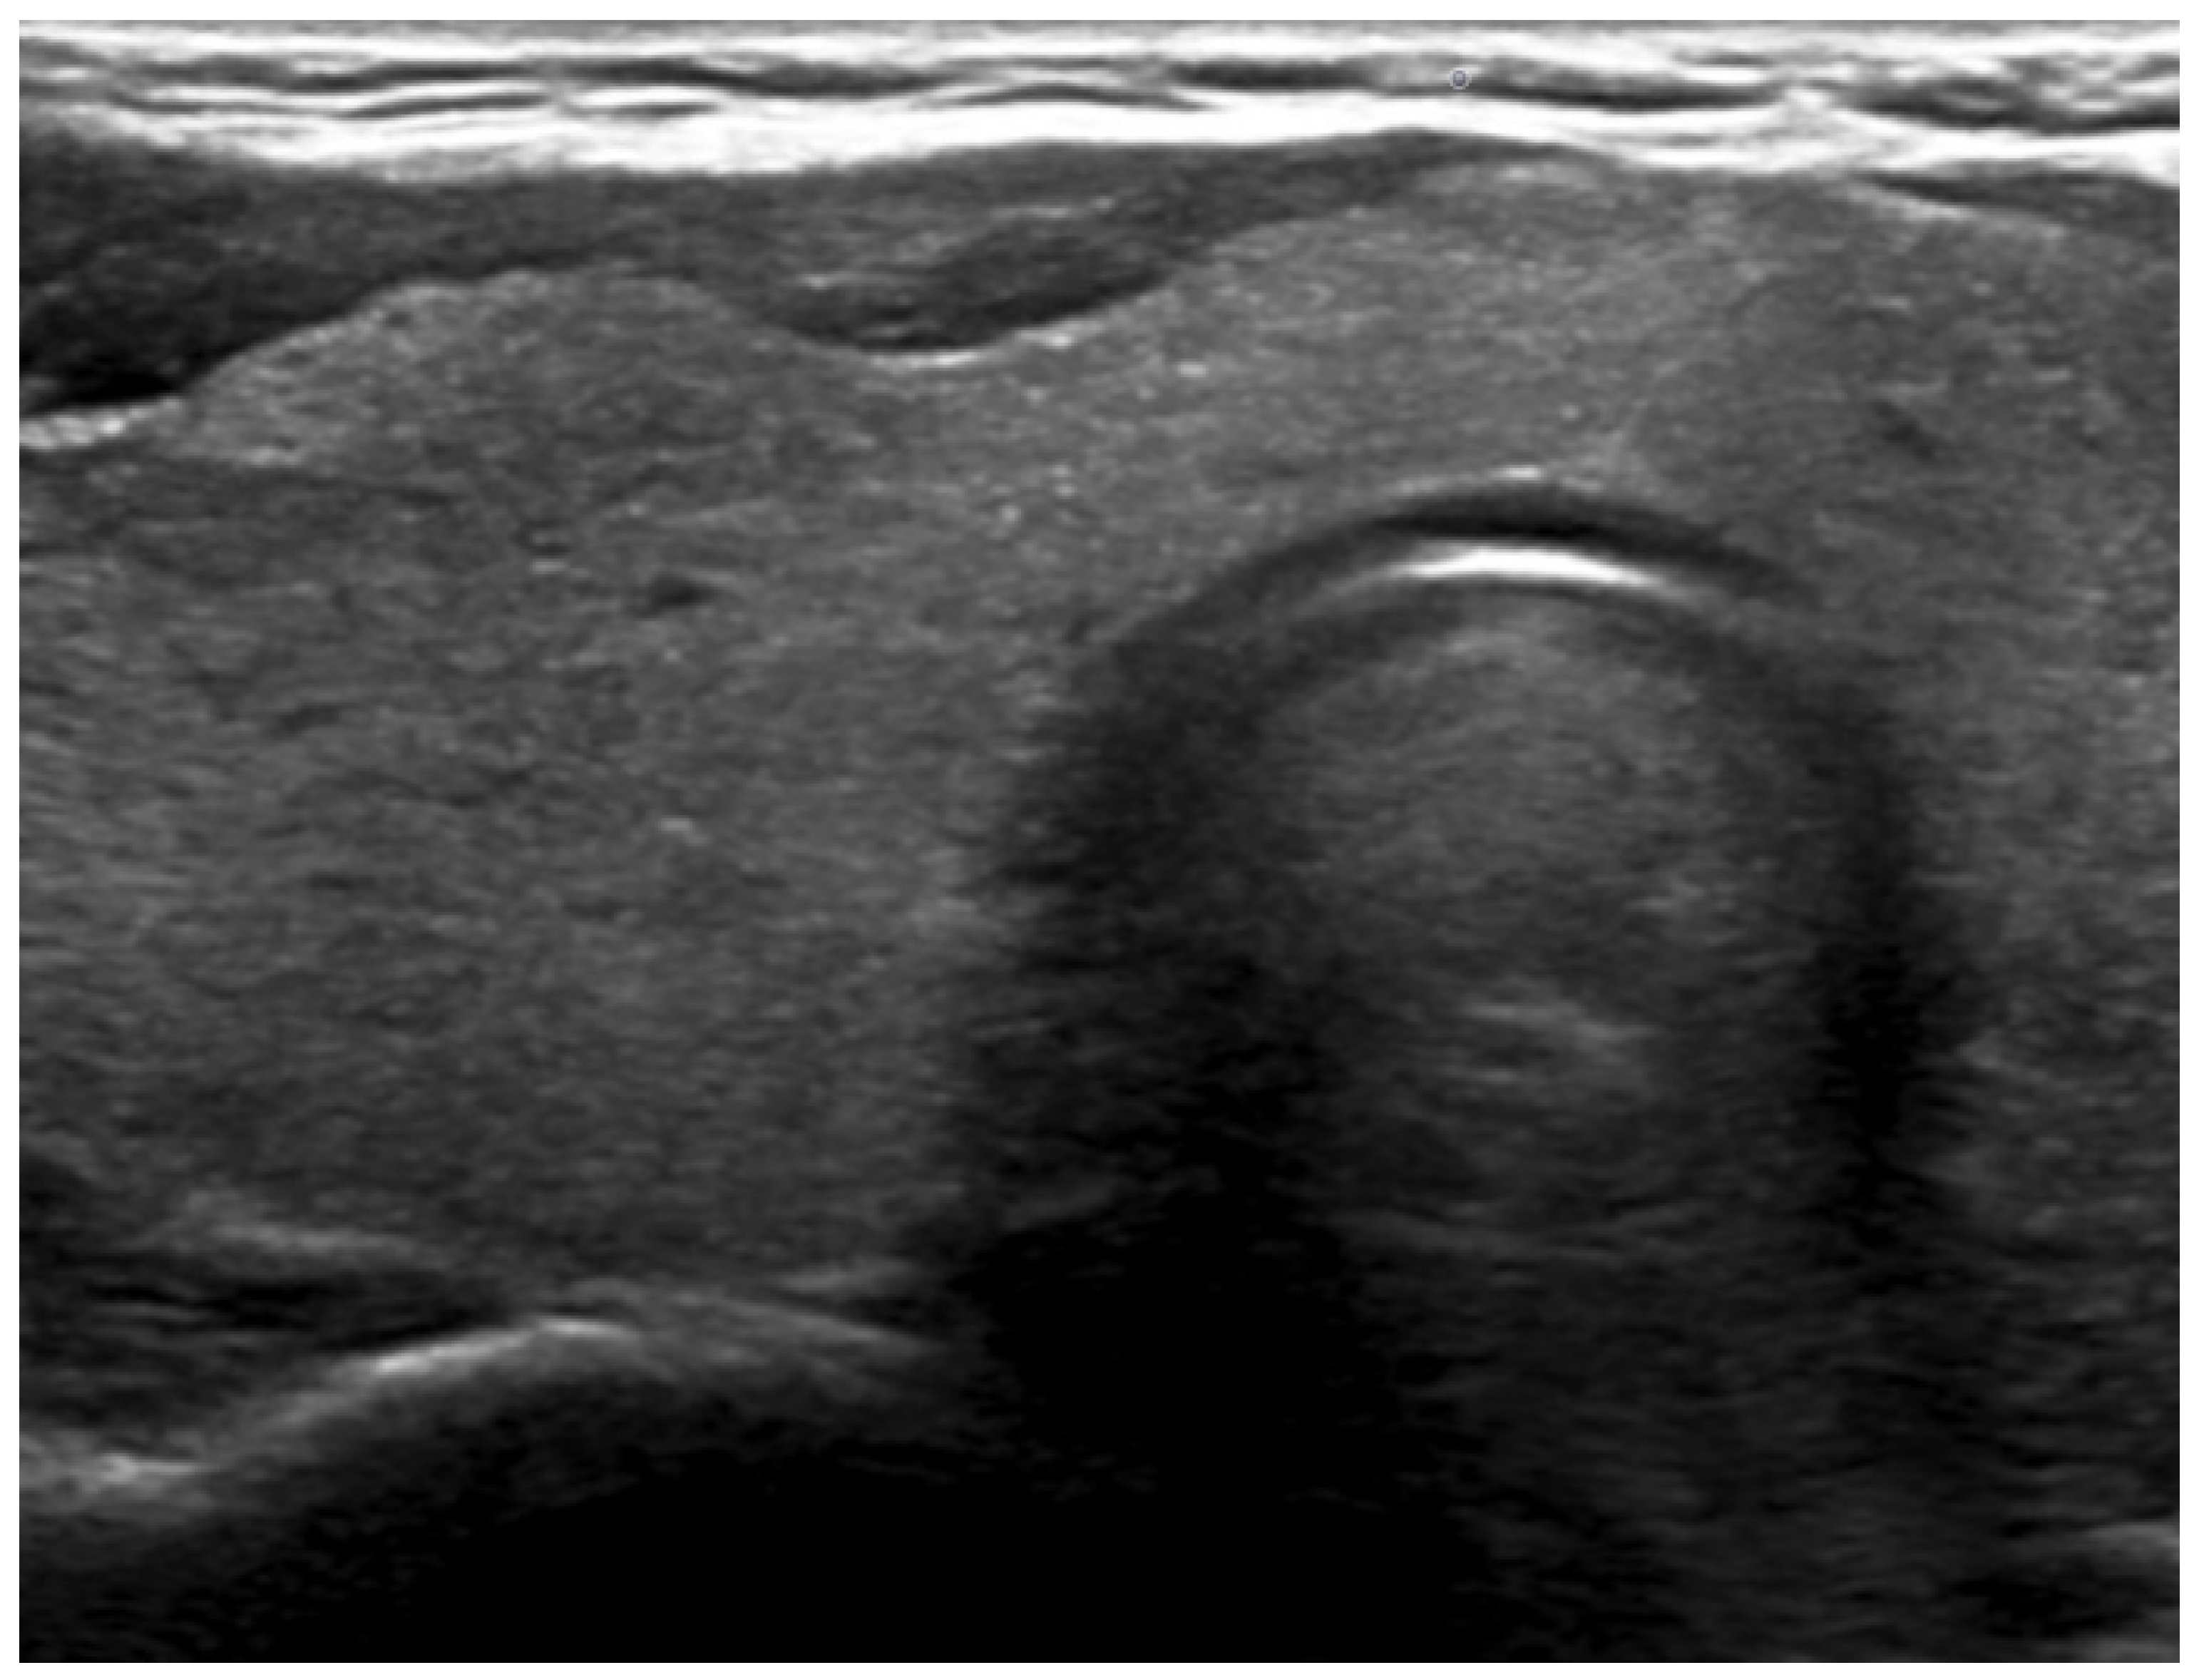

2. Case Report